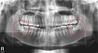

발치 과정은 환자에 따라 다르지만, 일반적으로 ‘파노라마’로 불리는 방사선촬영을 통해 사랑니의 상태를 파악하고 전문의의 판단 하에 발치를 진행하게 된다. 정상적으로 맹출한 경우에는 발치 과정이 비교적 간단하지만, 누워서 자라거나 잇몸 속에 매복되어있는 경우 발치 과정이 복잡해진다. 이런 경우 잇몸을 절개 한 후 사랑니 주변 뼈를 조금 갈아내고 치아를 조각내서 뽑아낸다. 사랑니가 턱뼈 속 하치조신경에 닿아 있거나, 통과하는 경우에는 발치의 난이도가 급격하게 상승하는데, 이 때 에는 구강악안면외과 전문병원이나 대학병원 같은 큰 병원을 방문하는 것이 좋다.

고려대학교 안암병원 구강악안면외과 전상호 교수는 “사랑니가 났을 때 꼭 뽑을 필요는 없지만, 문제가 생긴 경우에는 발치하는 것을 권유한다”며 “통증이나 불편함을 느끼기 전에 예방적 차원으로 미리 뽑는다면, 중3, 고1 겨울방학쯤에 뽑는 것을 권한다”고 말했다. 이어 “발치과정은 사랑니의 상태에 따라 다르므로 필요한 경우 3D CT을 촬영하여 사랑니 부근의 신경과 상악동 및 인접 중요 구조물의 근접성 정도를 정확하게 계산하고 안전한 발치를 행해야 한다” 고 밝혔다.